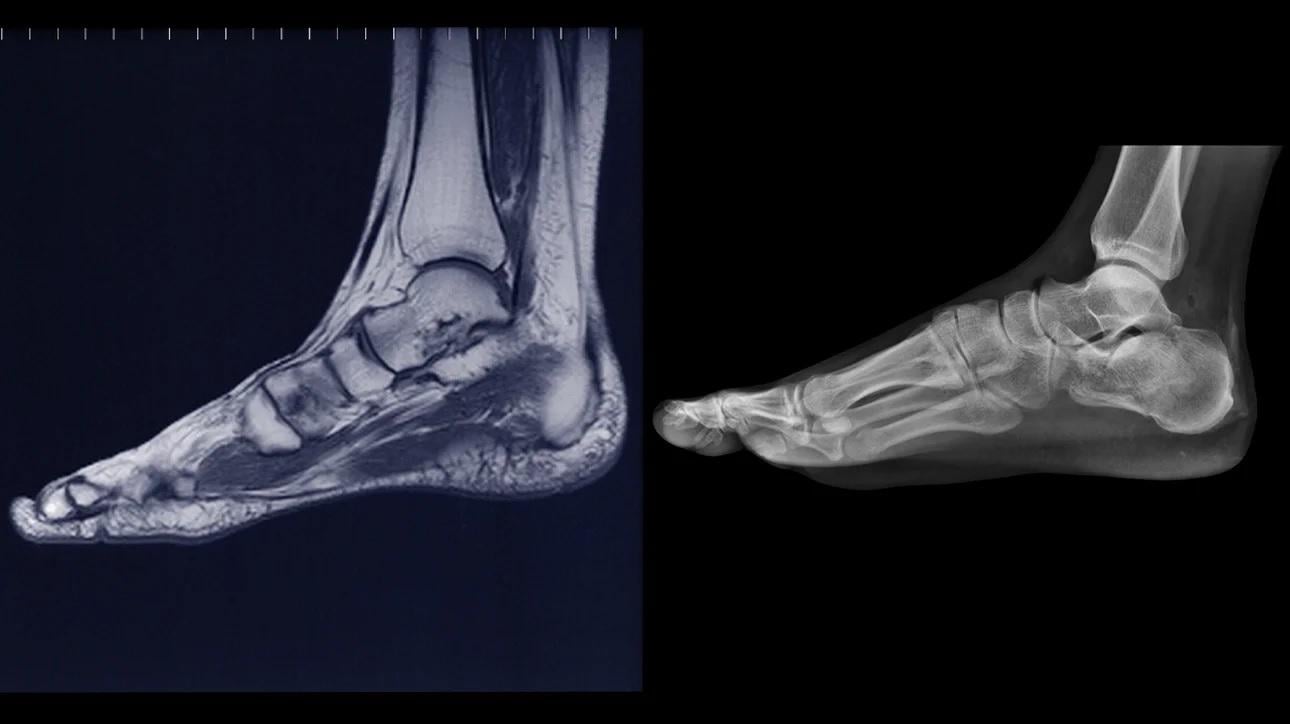

mri x光

磁力共振掃描是利用電池波技術製造影像,再配合電腦分析。它與X光不同之處,是X光含有輻射,而磁力共振則沒有。

如何「閱讀」磁力共振影像?磁力共振掃描分為T1T2兩類。於T1影像下,身體硬組織將以白色呈現。一些軟組織,例如是水或肌肉,則以黑色呈現。

物理治療師透過T1影像,已可看到很多答案,例如客人有否出現韌帶撕裂,倘若不幸出現撕裂,病情又有多嚴重。